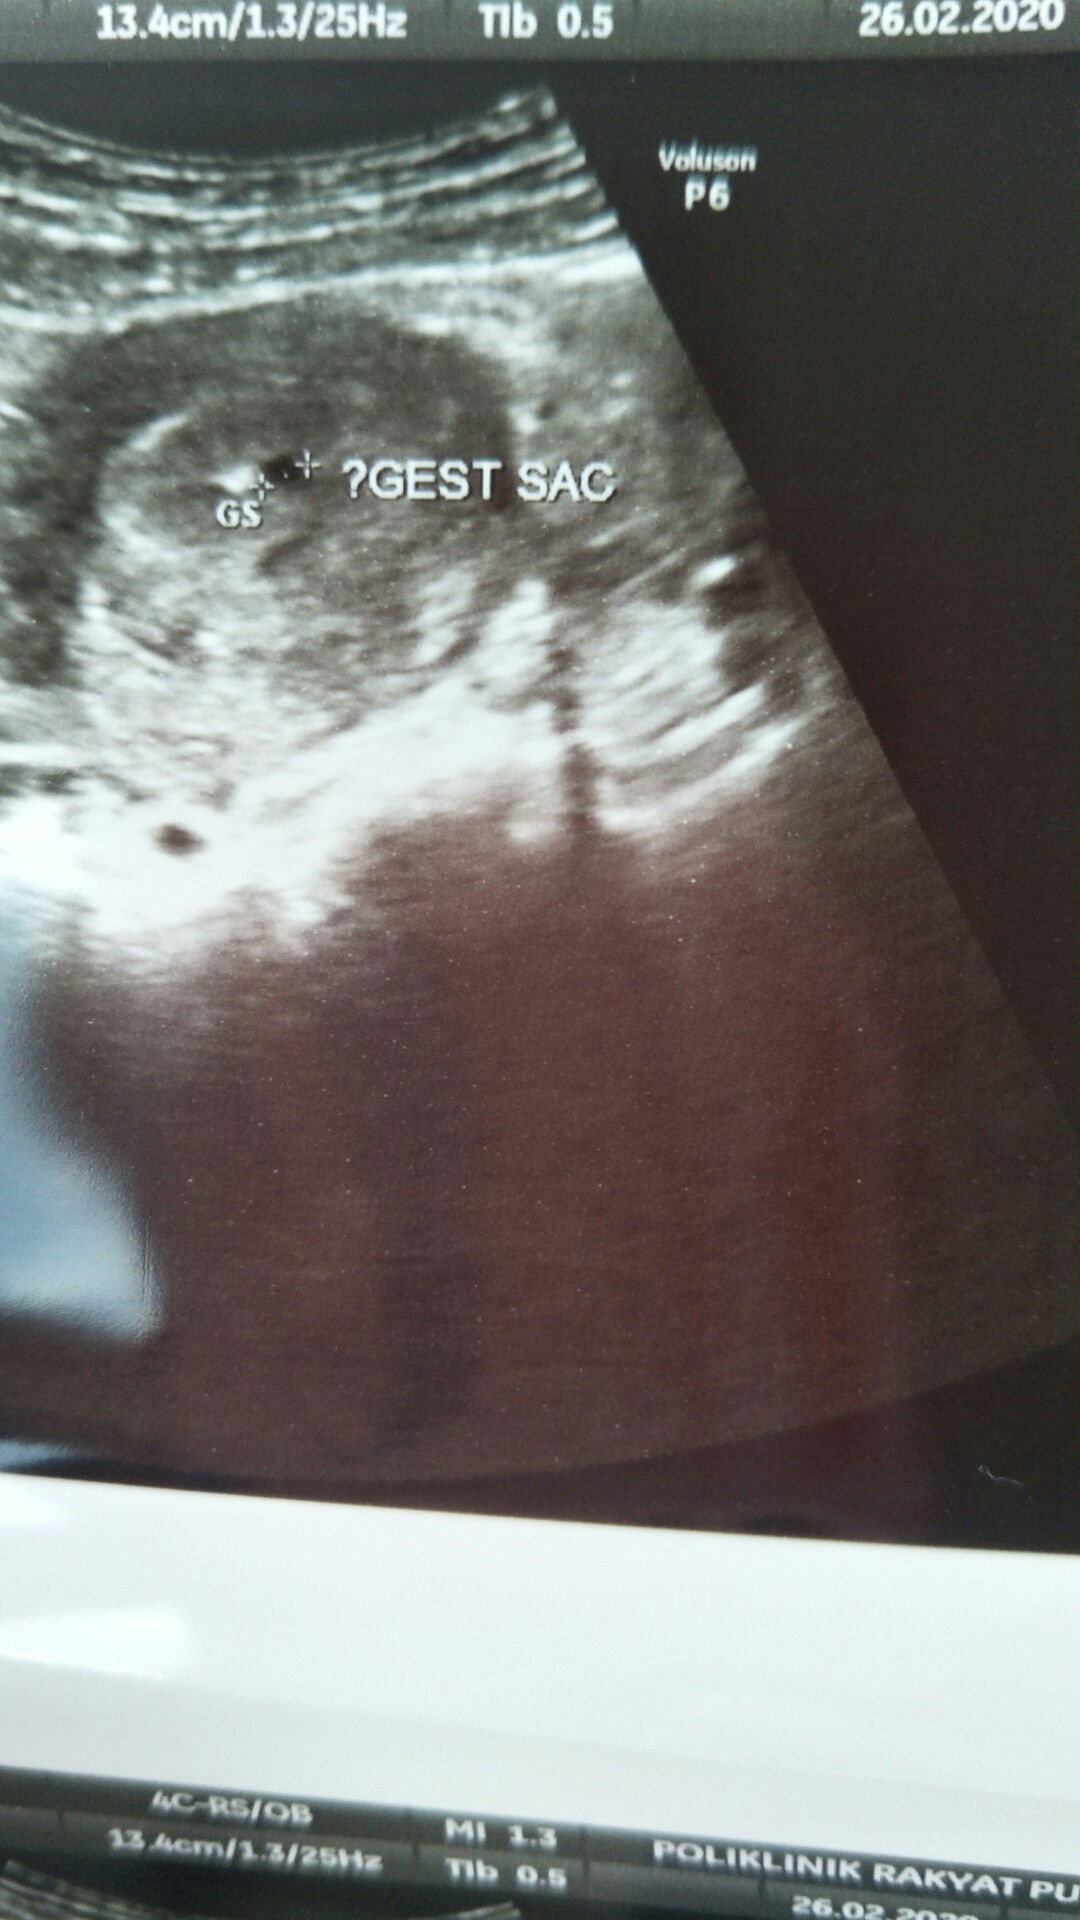

Masuk hari ini,ikutkan kiraan last 1st period dh masuk 9 week tp smlm kluar drh sdikit warna coklat,bngun td pagi ada lg drh kluar,jumpa doc scan kata blum npk apa2,ada kantung tp kecil sgt2. Doc suggest dtg 2 minggu lg utk scan. Risau sgt2 skrg. Ada x ibu2 d sini alamai pkra yg sama??